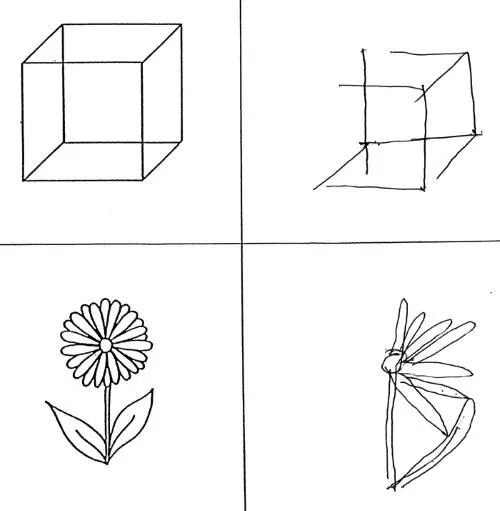

Такие пациенты бреют только половину лица и одеваются лишь наполовину. Попросите их скопировать простой штриховой рисунок цветка, и они нарисуют половину маргаритки. Дайте им тарелку салата, и они съедят половину. Поверните тарелку на 180 градусов, и они съедят остальное.

Справа – рисунки человека, страдающего «синдромом игнорирования»; он не замечал ничего, что находилось слева от него. (Масуд Хусейн, из статьи «Hemispatial Neglect», Parton, Malhotra and Husain, Journal of Neurology, Neurosurgery and Psychiatry 75, no. 1 [2004]: 13–21).